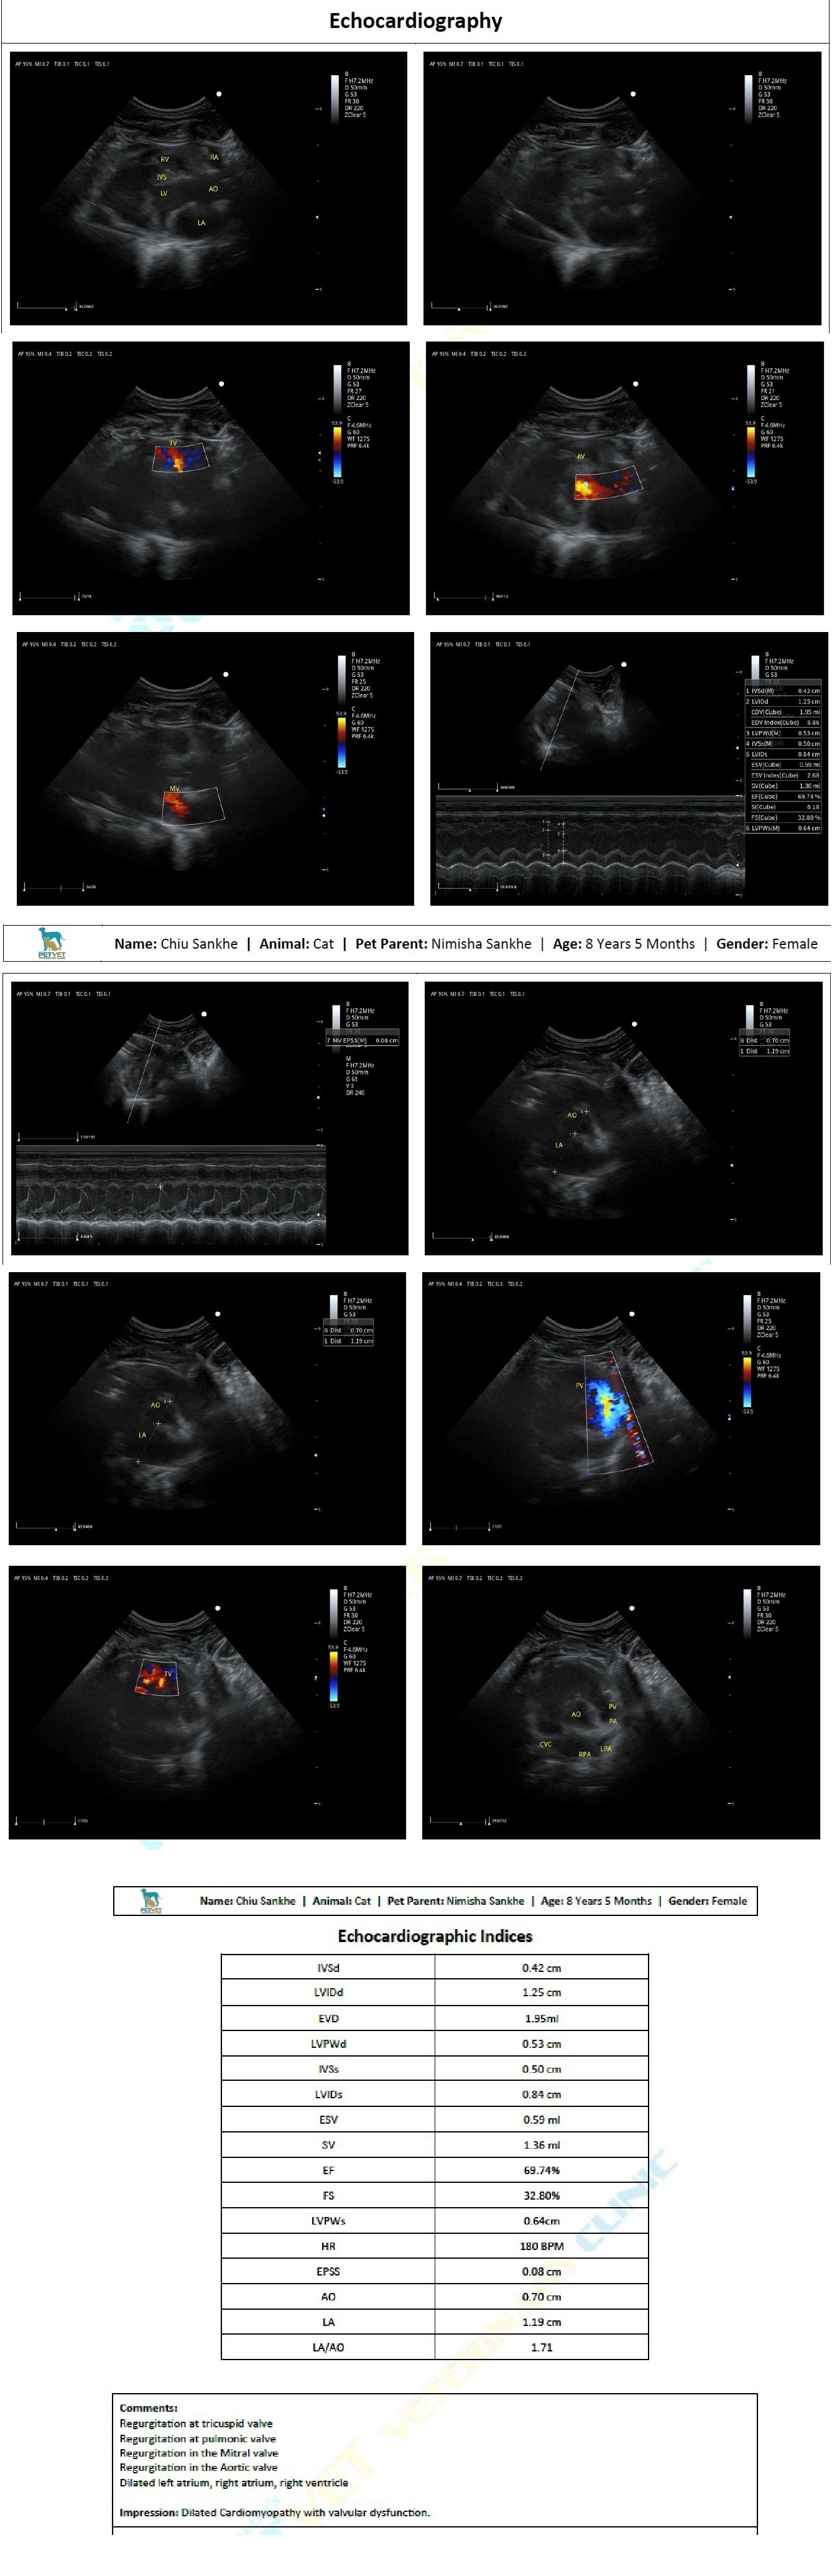

We've been doing the vet rounds since then and yesterday had a diagnosis of Dilated cardiomyopathy with valvular dysfunction after doing a 2d Echo of her heart.

Yesterday was the x-ray which still showed congestion. We did a 2d echo (scans attached). Vet said stuff like HCM, regurgitation, dilation. I had briefly read about HCM and got overwhelmed and didn't ask the vet for more details. But she sent me off with 30 days medicines (long list of meds below) and we'll do a repeat 2d echo after a month. ETA: she lost about 0.5 kg in the last 15 days.

I'm attaching her labs (Mar/Jul/Sep), x-rays (Aug/Sep/Nov/Dec) and 2d-echo (Dec).